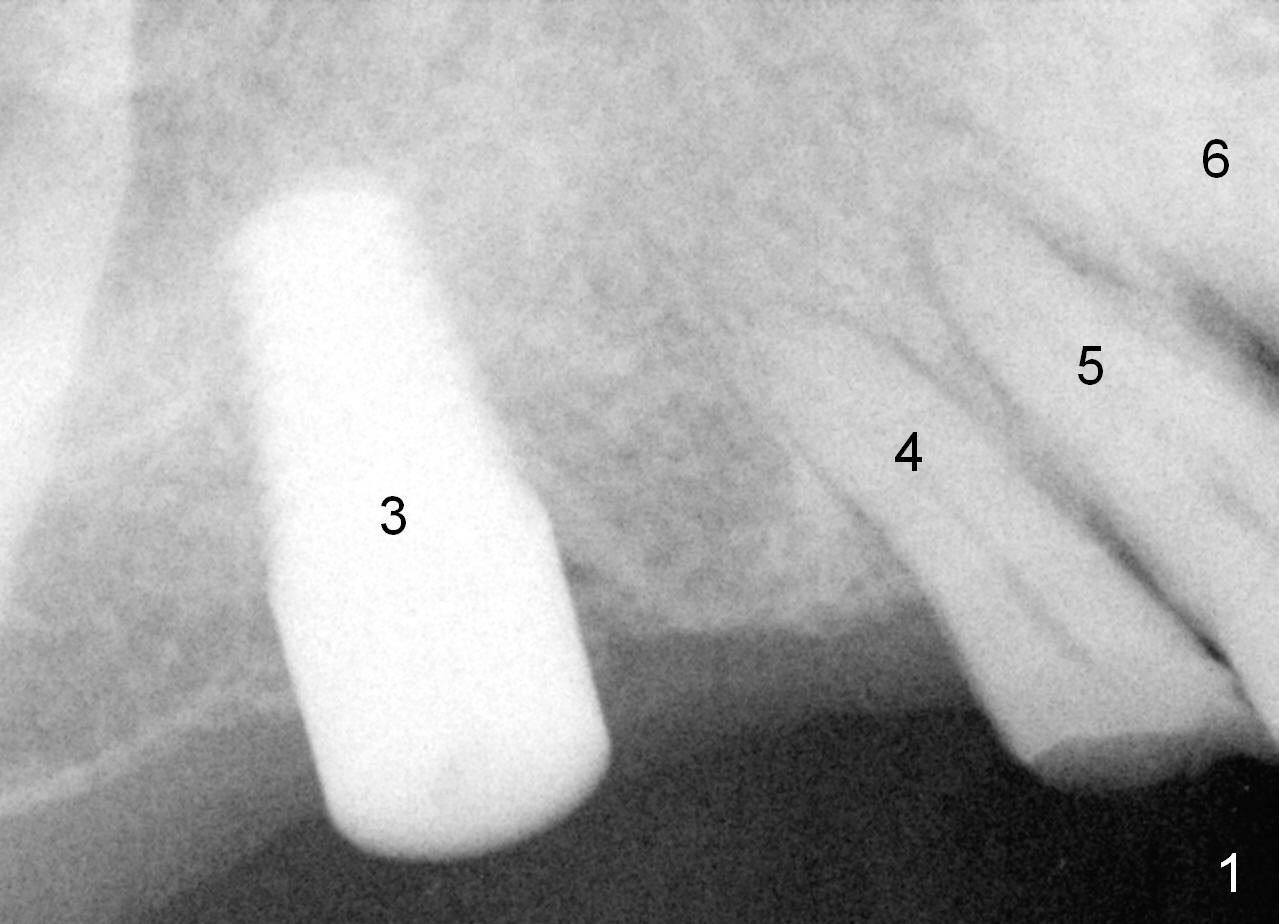

The implant at the site of #3 is intentionally placed distal as part of a plan to distalize the teeth #4-6 (Fig.1). Ortho started, but the patient did not want to pursue it. The most efficient way to terminate it is to dislodge every one of brackets/bands. When it is time for restoration for implants at the sites of #3 and 30, it is a challenge to deal with the space mesial to #3. The patient is planning to leave the country in 20 days. Fortunately he agrees to have an extra implant (Fig.2). It must be small in diameter. The initial osteotomy does not go on smoothly, approaching the apex of the tooth #4 (Fig.3 A). The osteotomy is moved distally and the trajectory is changed. It appears to be overcorrected (Fig.4). After re-adjustment, a 3.5x14 mm implant is placed with insertion torque between 15 and 20 Ncm (Fig.5). An abutment is placed with perio dressing applied around it as well as #3 after suturing. When the wound heals and before the patient leaves the country, the abutment is removed.